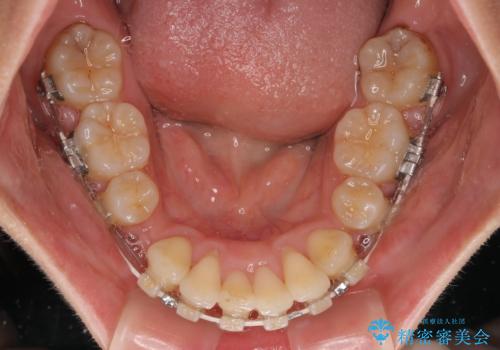

全顎的なデコボコと口元の突出感 ワイヤー装置での抜歯矯正で整った口元に

- 奥歯も含めて全体的なデコボコと前歯の突出感を気にして来院された患者様です。

上下左右第一小臼歯4本を抜歯し、ワイヤー装置にて矯正治療を行うこととしました。

想像以上に咬合力が強く、抜歯したスペースを閉じきるまでに長期間を要することとなりました。

前歯の突出感がなくなり、仕上がりには大変満足していただけました。